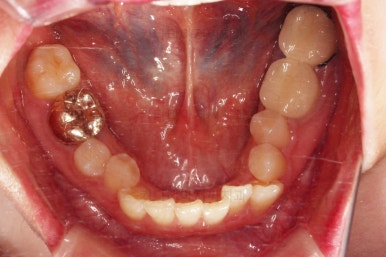

적절하게 디테일을 손보고 마무리를 합니다.

중간중간 보철된 치아도 있고, 위아래의 중앙선까지 100% 맞기는 힘든 상황이었지만 가급적이면 매우 잘 맞춰 드렸고요.

교합이라던지 가지런한 느낌도 좋네요.

우측만 위아래 뽑았지만 기능에는 문제 없이 교합을 마무리 했습니다.

부산치과교정 전후사진을 비교해 볼게요.

중심선도 원하시는만큼 갖추었고, 가지런한 느낌도 좋고요.

21개월만에 전반적으로 매우 만족할만한 치료 결과를 얻었습니다.